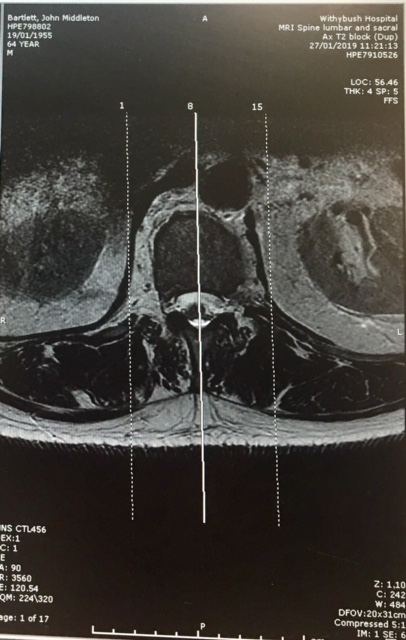

Just one mind boggling ruling was Judge McRae’s refusal to allow the Spinal Surgeon time to give his full evidence in the Witness Box JB – 26, or even to show the Jury the all important x-rays of my injuries. New MRI Images, below (New MRI Report), submitted to the CCRC in 2019 clearly showed the same accident damage the jury were prevented from seeing by my Trial Judge on 11th Nov 1994.

In 2019 this new MRI Report confirmed what the Spinal Surgeon had originally identified back in 1993:

“Both exiting nerves are flattened, more on the right side… severe narrowing of the L5 – S1 exit foramina, more on the right side, compromising the exit nerves”:

In 2023 the CCRC accepted new MRI scans[63][64] and acknowledged that Judge MacRae had wrongly curtailed important medical evidence, preventing it from being heard by my Jury. The new MRI scans confirmed multiple spinal fractures with two broken vertebrae, one having being knocked forward in my lower spine by a quarter of an inch, flattening and severely narrowing the exiting nerves to my right leg, causing a Spondylolisthesis at level L5 S1. These scans proved my injuries were caused by a serious traumatic impact, consistent with my 1988 horse riding accident and evidence the Spinal Surgeon had attempted to tell the Jury[65] but, as with so many cases submitted to the CCRC, they failed to do anymore than a simple desktop Case review. They refused to investigate the inaccurate police timeline and refused to interview witnesses and declined to refer my Case back to The Court of Appeal.